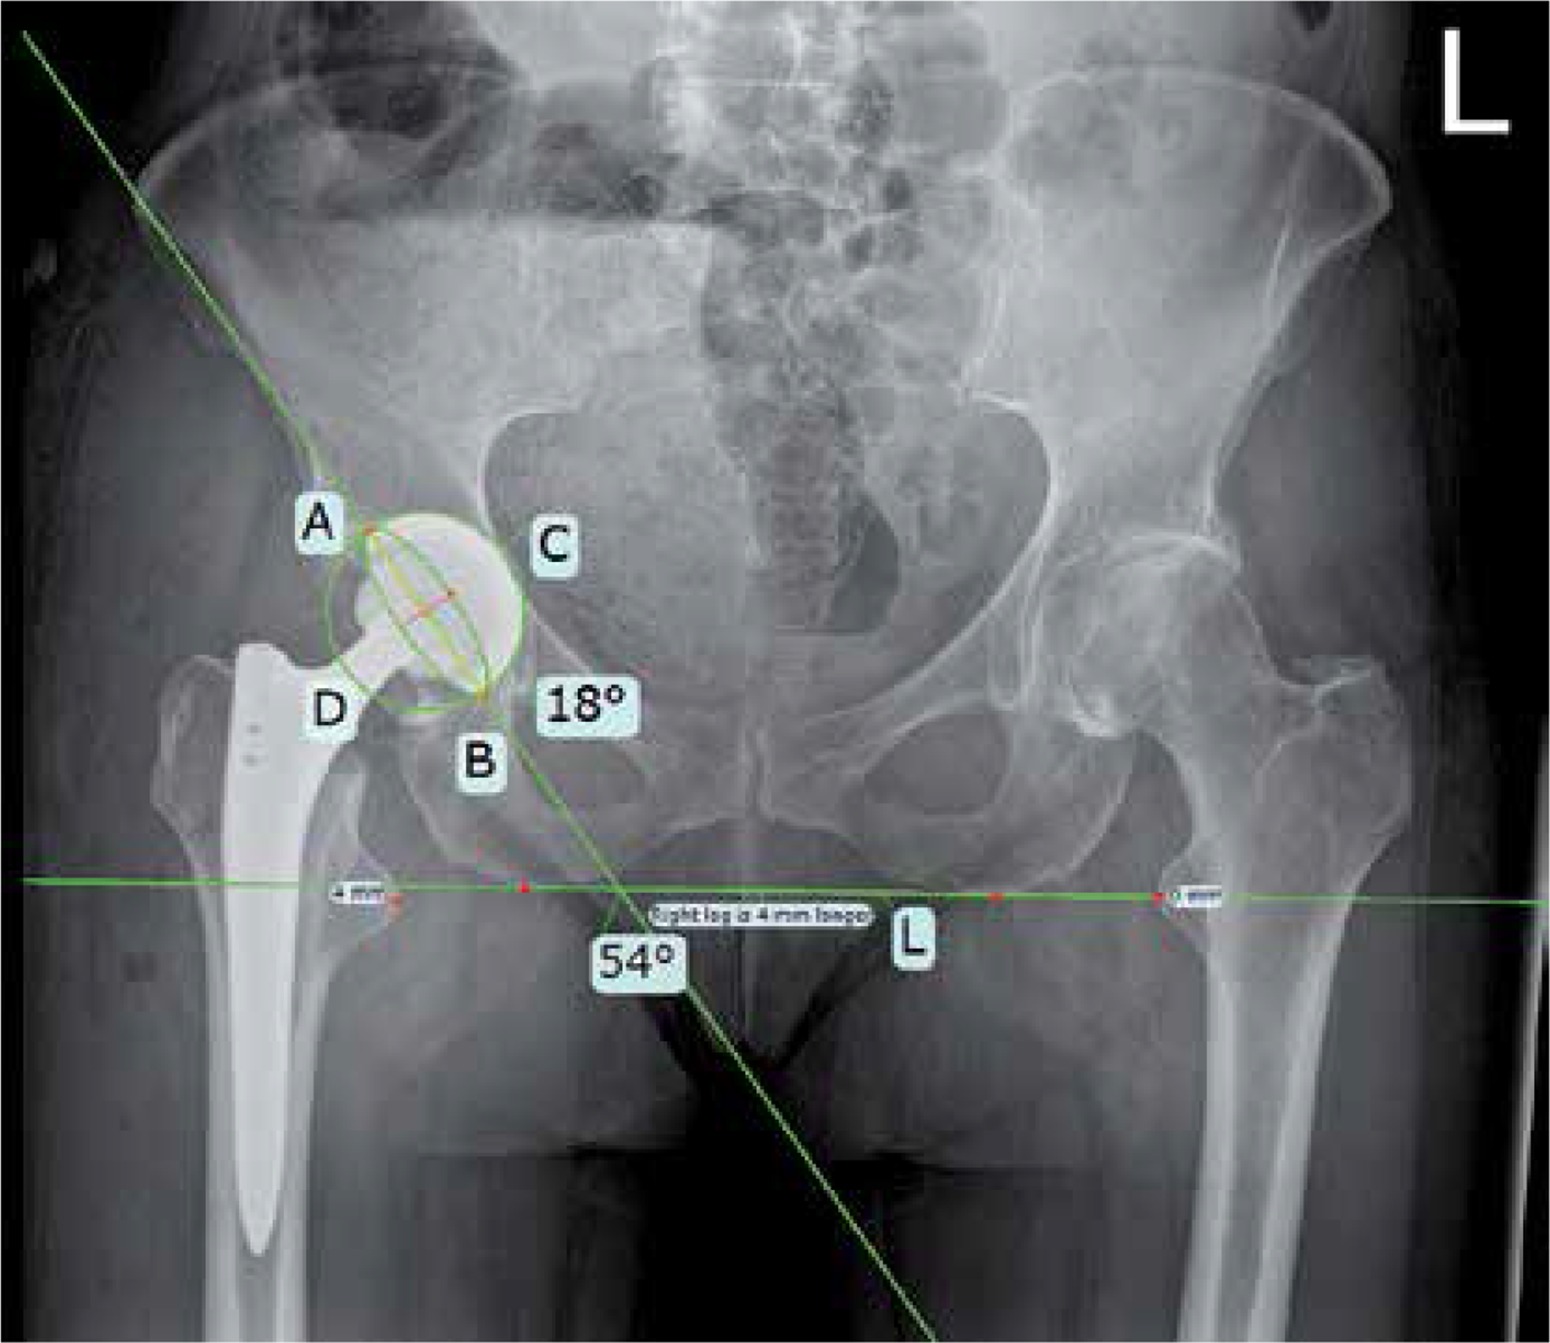

Cup anteversion and inclination were measured from AP pelvic radiographs according to the method first described by Bachhal et al. [21] (Figure 2). The AP pelvic radiographs were also used to measure hip offset, horizontal and vertical center of rotation as well as the leg length in a previously published manner [22, 23] (Figures 3–5). All radiological measurements were performed by one of the authors (G.K.) using digital templating software (TraumaCad, Brainlab AG, Munich Germany).